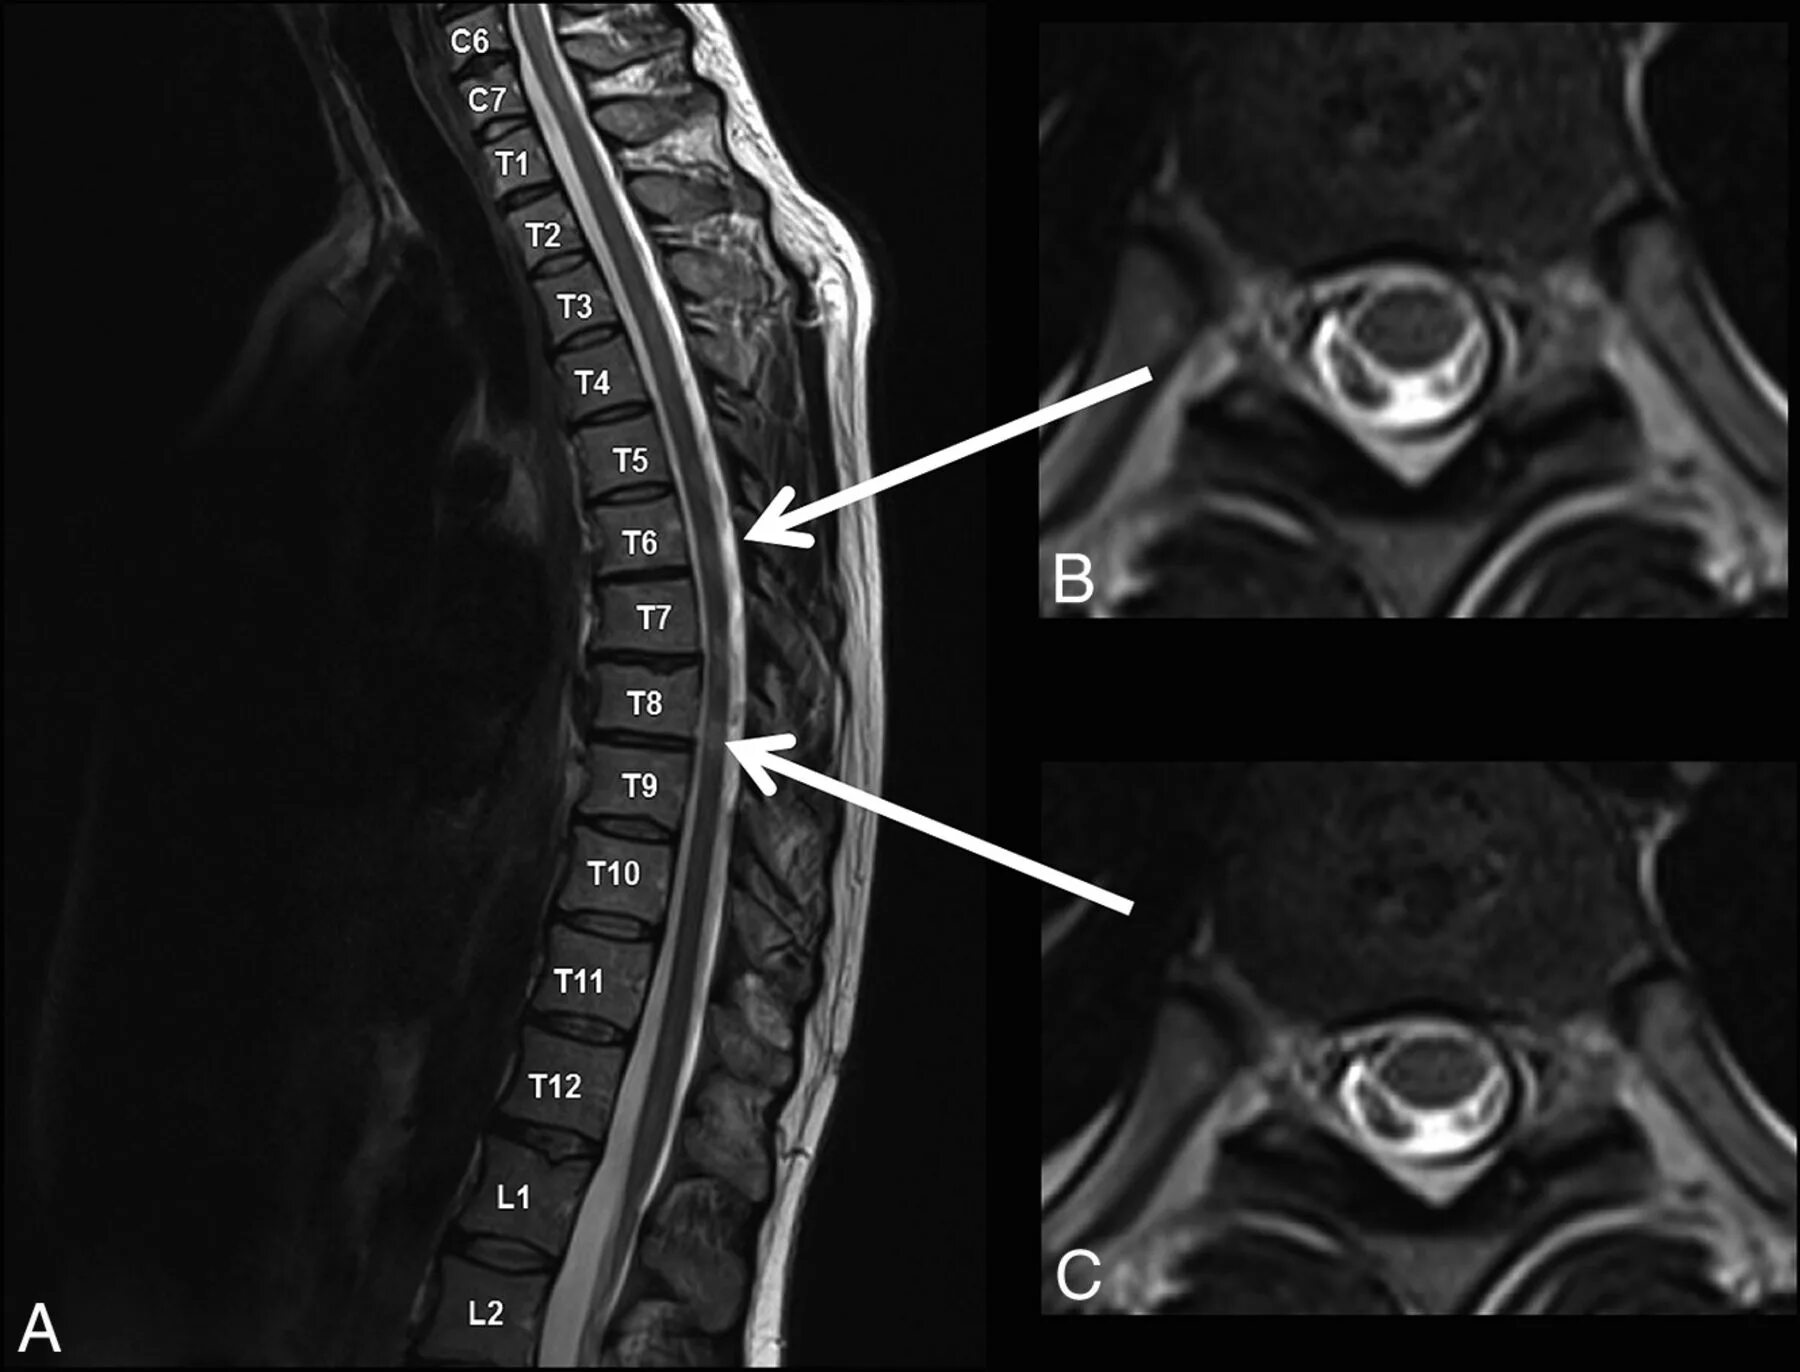

Spine mri